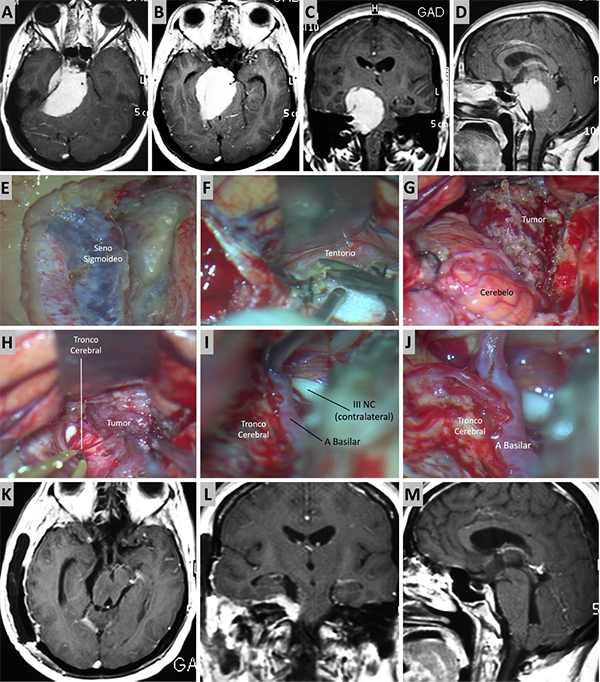

Figura 4. Caso ilustrativo #2. MRPC con implantación petroclival, extensión a la fosa media y compromiso de la incisura tentorial. Paciente con audición conservada. A. Corte axial sobre la región clival media. B. Corte axial sobre la región clival superior. Corte Coronal. D. Corte sagital donde se observa el efecto compresivo sobre el tallo cerebral. E-J. Se realizo un abordaje retrosigmoideo. K-N. Se muestra las imágenes en distintos cortes con resección quirúrgica completa.

Figura 5. Caso ilustrativo #3. A-D. Resonancia que muestra MRPC con implantación clival. E-J. Se realiza un abordaje retrosigmoideo, consiguiendo la liberación del complejo VII-VIII del tumor y su resección completa. K-M. Resultado imagenológico postquirúrgico.

Figura 6. Caso ilustrativo #4. Meningioma de la MRPC con implantación petrosa anterior. El paciente presentaba neuralgia del trigémino atípica derecha. A-D. Imágenes por RMN pre operatorias. E-J. Se realiza un abordaje retrosigmoideo consiguiendo la resección total del tumor. K-M. Con ayuda de endoscopio y lente con angulación de 30º se inspecciona el área sin encontrar remanente tumoral. Se observa liberación del nervio trigémino. K-M. RMN postoperatoria que muestra resección total.